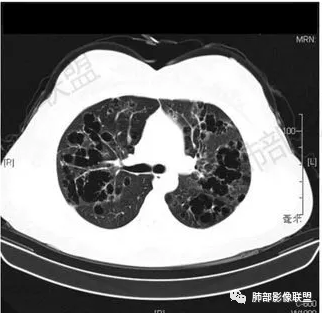

女,46,活动性气喘1年。苯吸入史半年。胸部CT:两肺弥漫囊腔,上至肺尖,下至肋膈角,形态类似小囊腔。考虑:LAM,鉴别LIP,BHD,PLCH等。

双肺弥漫大小不一薄壁含气囊腔,囊间肺组织正常,正常肺背景,肺尖肺底受累;青年女性,气喘,支持LAM

CT表现:双肺弥漫大小不等的薄壁囊腔,囊壁<2mm,外形规则,血管影多位于囊腔周围,囊腔之间肺组织正常,随着疾病进展到晚期,囊腔变大、增多,不可胜数,囊腔可融合成较大的囊,与肺气肿相似,形成间质性肺纤维化。部分病例可出现结节影。